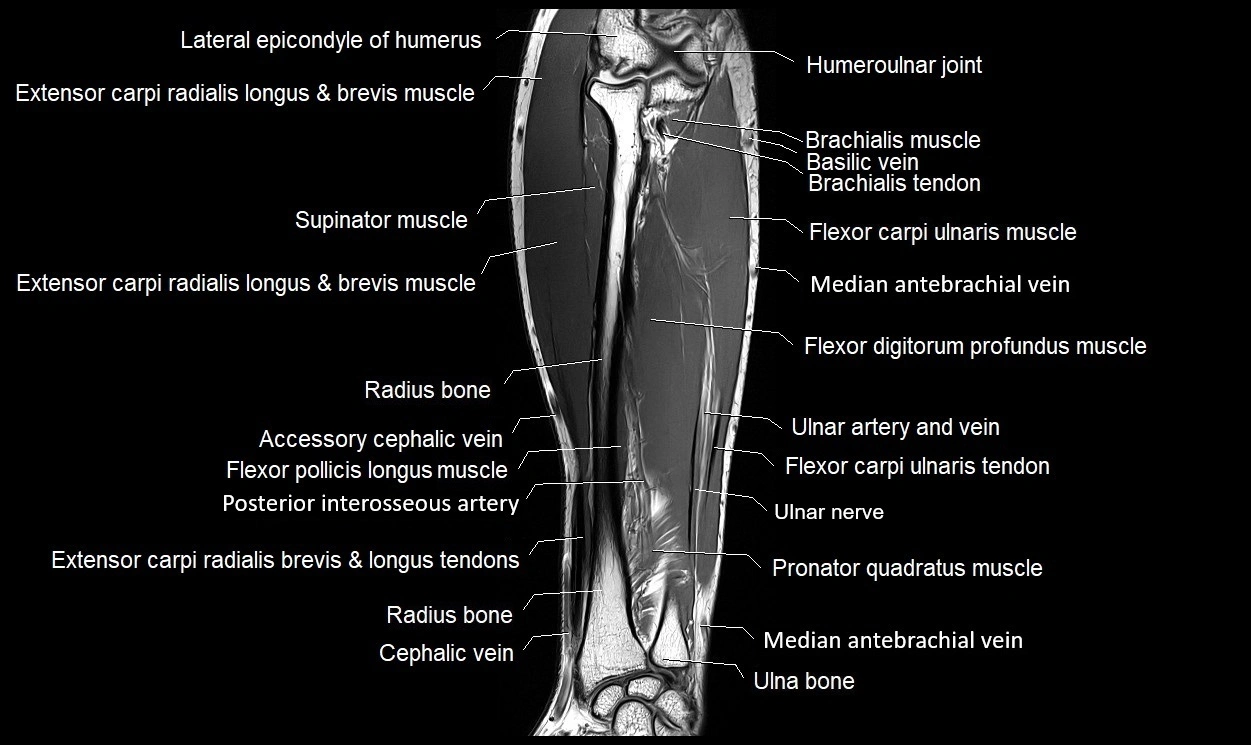

image

MRI images